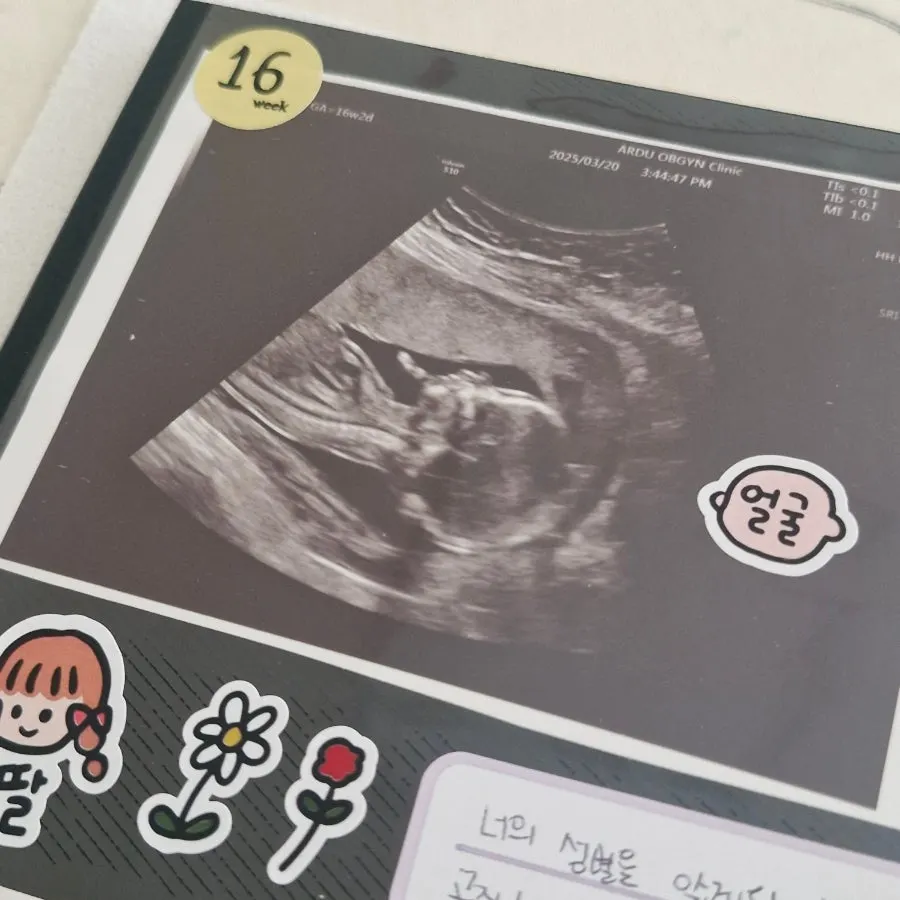

임신 16주에는 2차 기형아검사를 했다.

다행히 아기는 주수에 맞게 잘 자라 있었고,

초음파에 아기 갈비뼈나 척추뼈가 보이는 게 너무 신기했다. 이제는 아기 머리크기, 배크기, 허벅지뼈 길이를 합쳐 무게도 재주신다. 아직 200g인데 제법 사람 같았다.

드디어 성별도 알았다! 아기가 다리를 오므리고 있어서 애매하다고 이번엔 17분이나 초음파를 봐주셨다.

아기의 성별은 딸!